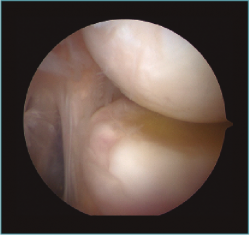

La pared anterior está formada por la cápsula articular, que va de techo a suelo del compartimento. La cápsula se podrá observar hipertrófica en casos de rigidez de codo. Adyacente a la cápsula articular se localiza el tejido sinovial. La hipertrofia de este tejido debida a enfermedad propia de la sinovial o reactiva se presenta como una proliferación localizada o generalizada (Figuras 6 y 7). La proliferación sinovial puede presentarse asociada a la formación de cuerpos libres (Figura 8).

Figura 6. Sinovitis focal adyacente a la coronoides. Codo derecho, visión con óptica de 30° desde portal lateral.

Figura 7. Sinovitis sobre la cápsula anterior y condromalacia leve en cabeza radial. Codo derecho, visión con óptica de 30° desde portal medial.